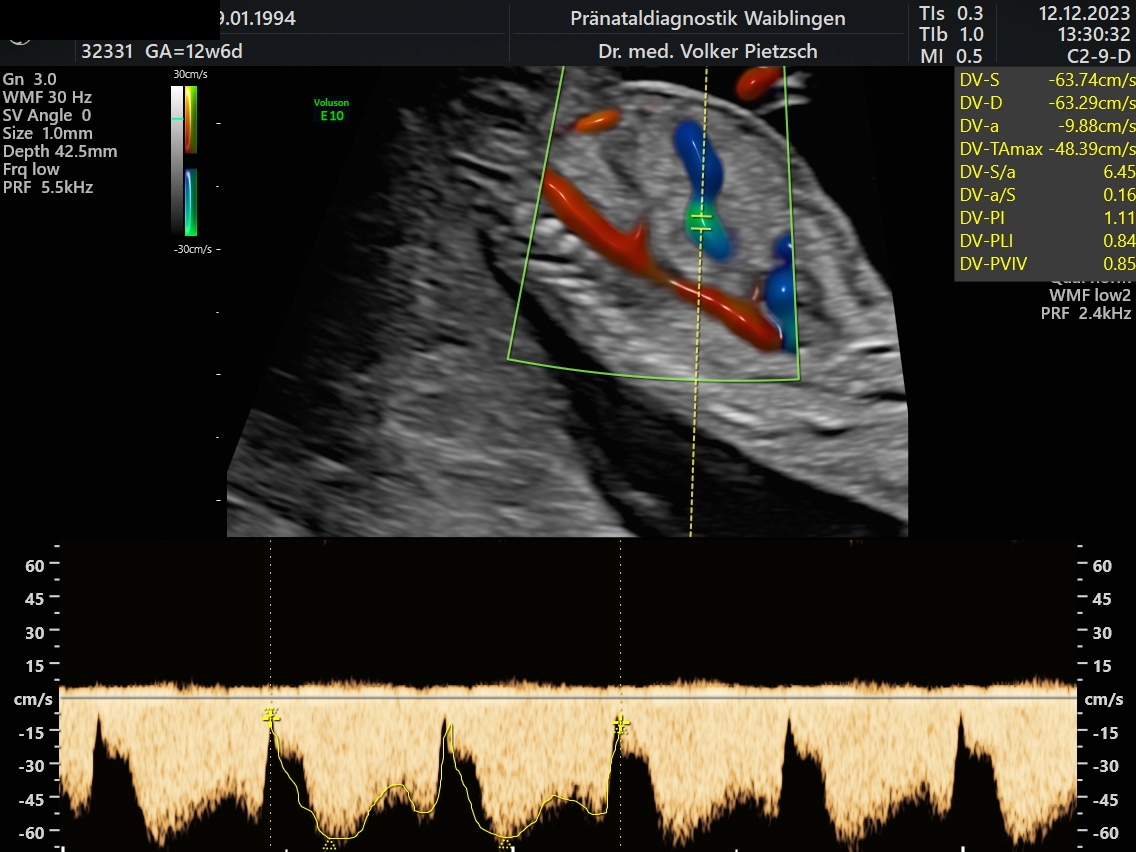

Der Blutfluss im Ductus venosus